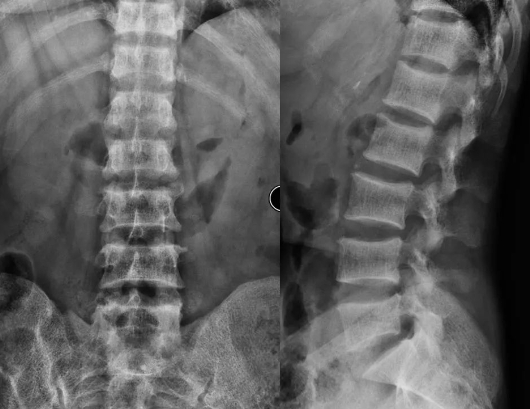

UBE经对侧椎板下入路治疗远端脱垂型腰椎间盘突出症!